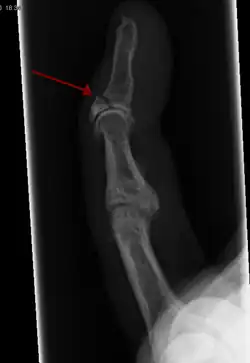

Compare healthy bone with different types of fractures:

(a) closed fracture

(b) open fracture

(c) transverse fracture

(d) spiral fracture

(e) comminuted fracture

(f) impacted fracture

(g) greenstick fracture

(h) oblique fracture